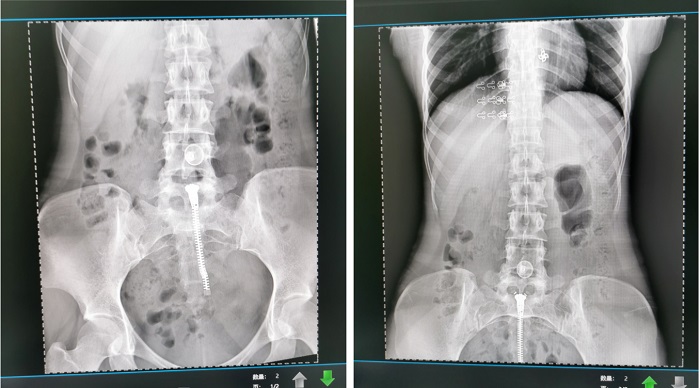

普利德懸吊DR采用高品質(zhì)平板探測器,滿足人體頭部、胸部、腹部、腰椎、四肢等部位的數(shù)字攝影檢查,成像速度快,圖像質(zhì)量高,可對肺野內(nèi)細微結(jié)構(gòu)顯示清晰,病變檢出率高,而且降低受檢者所接受的輻射劑量,這些優(yōu)勢在體檢篩查中對早期發(fā)現(xiàn)病變具有重要的意義。